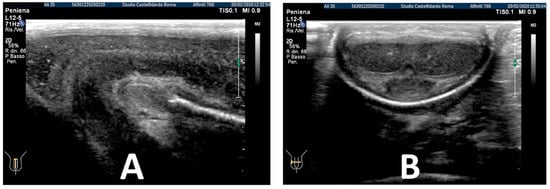

At the end of the first treatment cycle, at follow-up, the patient filled out the IIEF questionnaire, and the score was 26. We then observed a left penile curvature with a decreased angle (to 25 degrees). The pain in the penis had gone. The penile ultrasound showed the following dimensions: 6.33 × 5.58 × 2.66 mm (49 mm3 = volume) (Figure 2).

Figure 2. Ultrasonography of the penis after the 1st therapy cycle (longitudinal and axial views).